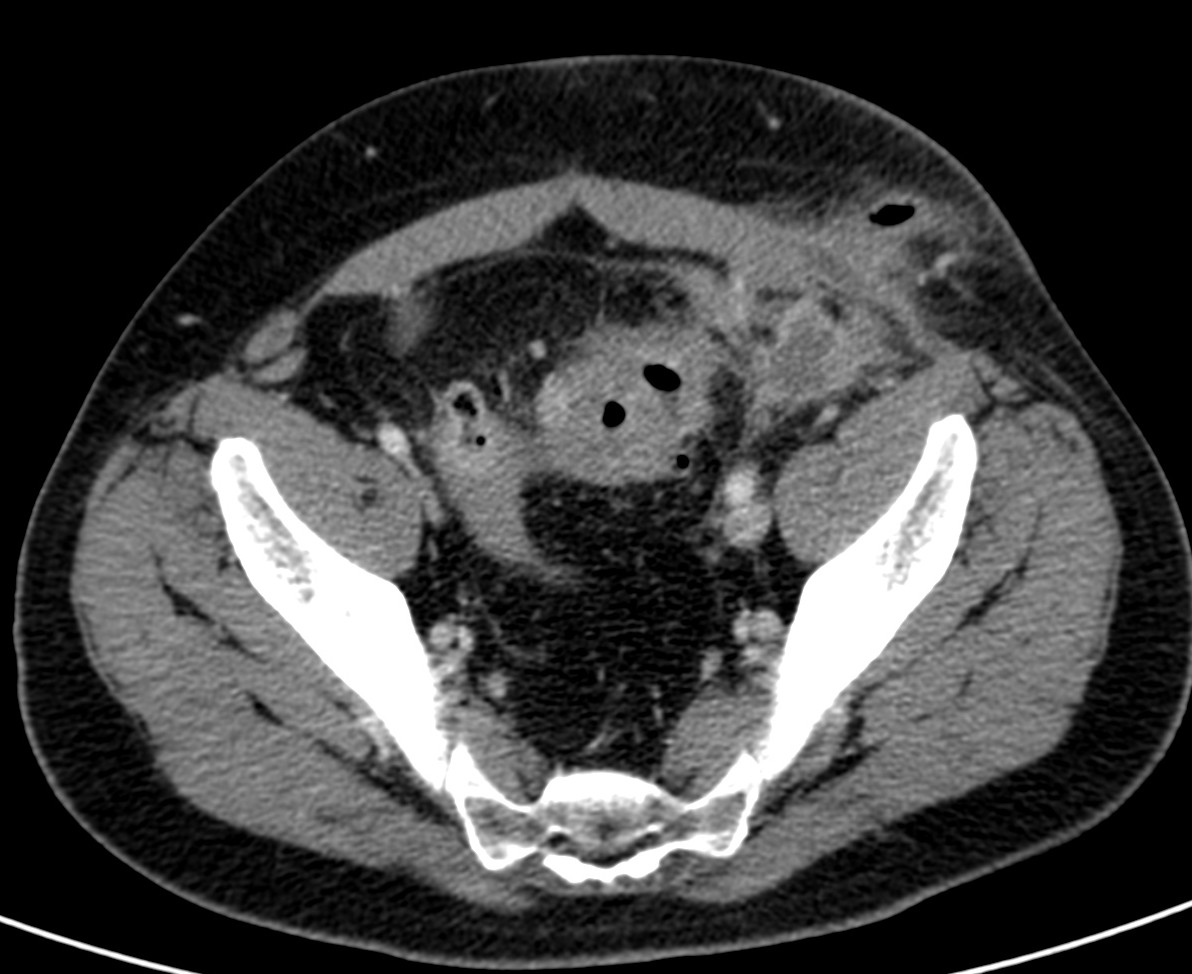

Se completa el estudio con TC de abdomen con contraste i.v.

TC ABDOMEN: Se confirman los hallazgos vistos en ecografía. Se aprecia un engrosamiento mural > 4mm de un segmento aproximado de 5.5 cm de longitud con infiltración de la grasa adyacente y sin visualizar colecciones ni gas extraluminal, hallazgos compatibles con diverticulitis aguda no complicada.

CONCLUSIÓN: Diverticulitis aguda no complicada. HINCHEY grado 0